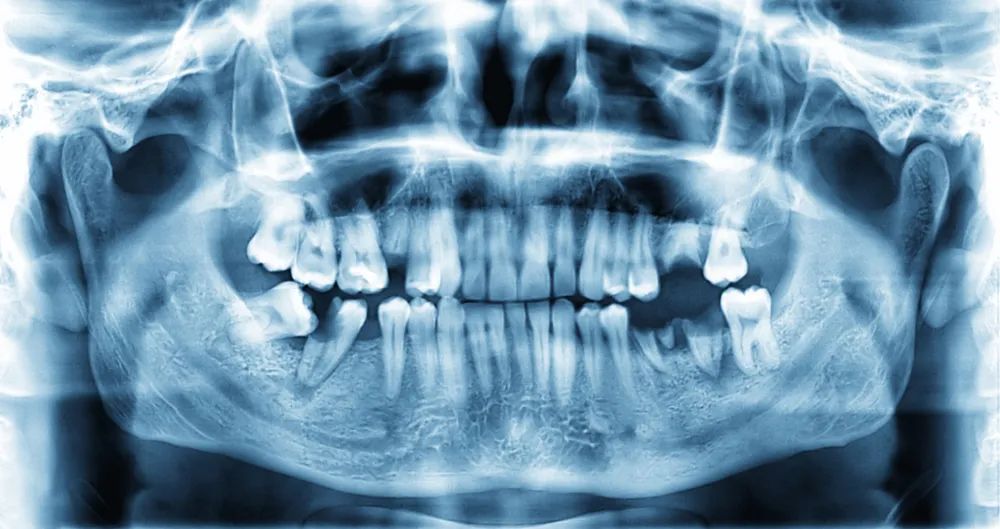

X 光下的牙齿

图片来源:站酷海洛

也正是由于 X 光片的这个特点,如今的 X 光片依然被最多用于骨骼、牙齿疾病的诊断以及各种介入治疗中,用于判断有无骨折、牙齿的状态、植入物的位置、以及体内有无结石、异物等高密度的物体等。